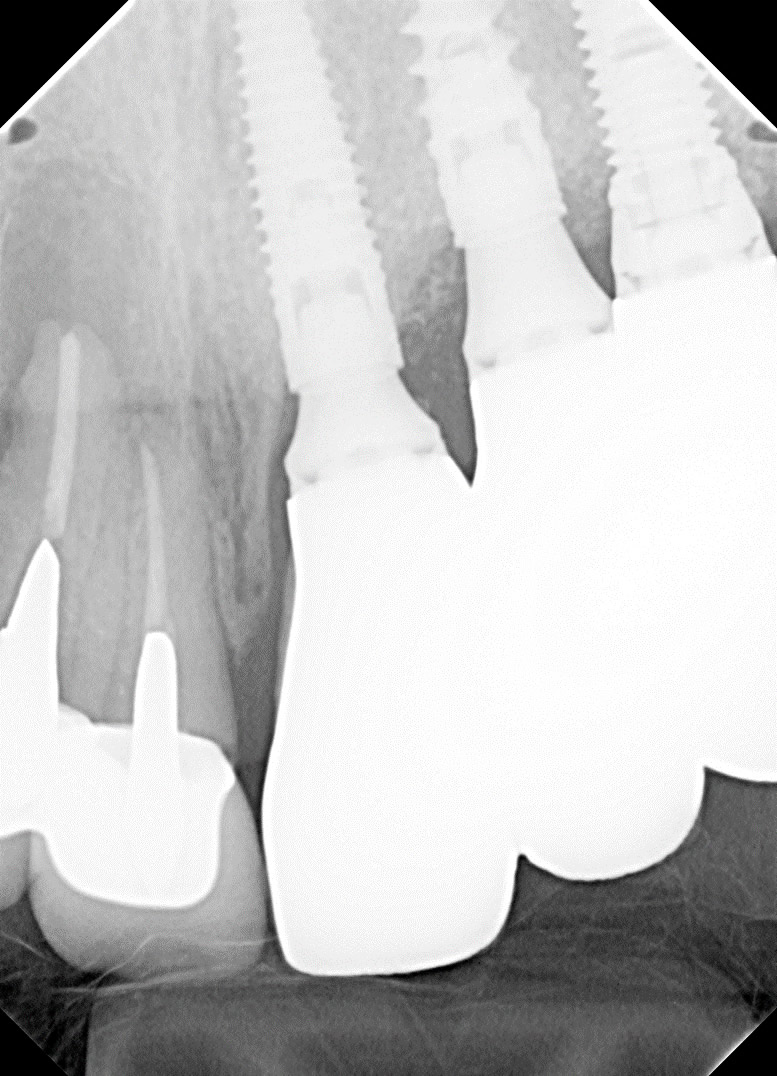

術後X線写真です 計画通りの治療が行えました

骨造成と上顎洞底挙上によりインプラントを完全に骨の中に入れる事が出来ました

術後のレントゲン写真です 計画通りの治療が行えました

最終補綴物装着時X線写真